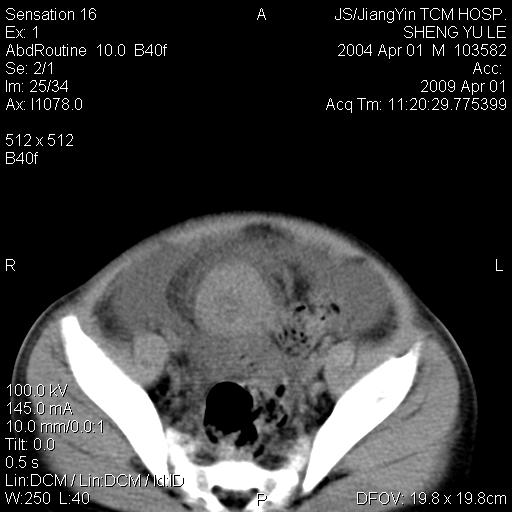

m,5岁。尿痛尿频数天。既往无病史。ct平扫腹盆腔积液。膀胱壁明显增厚。另可见心包增厚。wbc5万,骨髓穿等结果。请指教。

膀胱影像表现结合临床应该是急性膀胱炎症,但为什么有腹水呢?双肾输尿管无扩张,泌尿系压力应该不大不至于引起尿外渗,应该是腹膜感染引起的,但楼主没有提及相关症状,腹膜及膀胱结核?患者白细胞5万(结核不至于这么高啊),脾脏增大,是不是有白血病?进一步检查。。